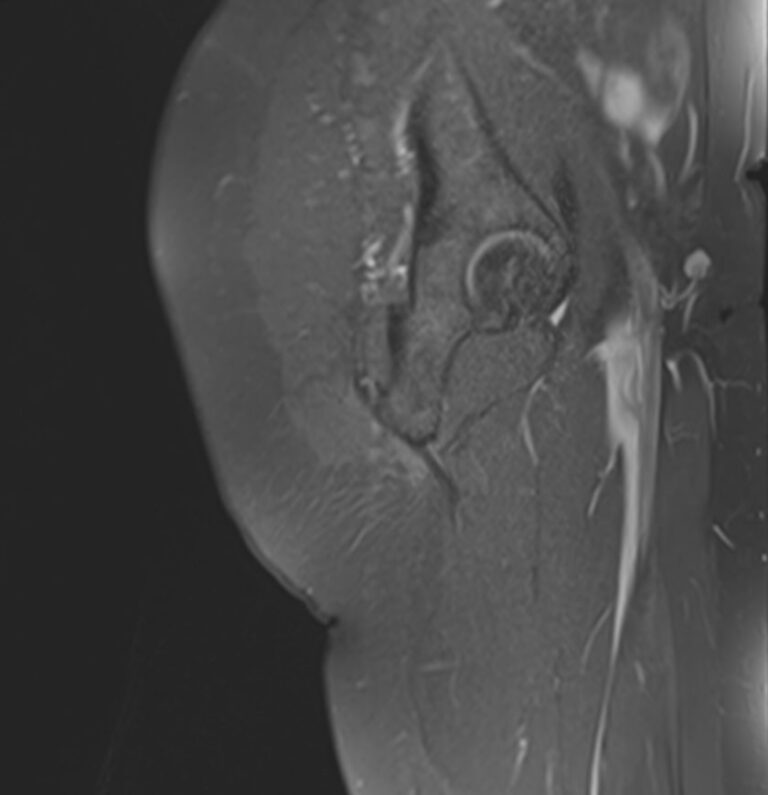

МРТ данной анатомической области выполняется в большинстве случаев в стандартном режиме без применения контрастного усиления. Однако при подозрении на развитие опухоли необходимо введение контрастного препарата. Для этого используется контрастное вещество, созданное на основе гадолиния (металл, обладающий особыми свойствами в зоне действия магнитного поля). Контраст избирательно накапливается в очагах поражения и обусловливает их яркое свечение под влиянием магнитного поля томографа. Это позволяет, в частности, выявлять опухоли на ранних стадиях развития и дает исчерпывающую информацию о структуре опухолевого образования, его границах, степени кровоснабжения и распространения на близлежащие органы и ткани.

- Доброкачественные и злокачественные опухоли, которые располагаются в мягких тканях ягодичной области.